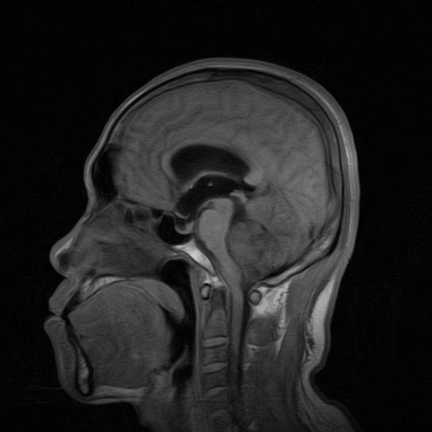

标题: MRI2064:少见病例。男性52,视力下降多年。 [打印本页]

标题: MRI2064:少见病例。男性52,视力下降多年。

四脑室区见混杂信号占位影,脑室系统扩张明显,临近结构显著受压称位,患者52岁,多考虑室管膜瘤可能性大

考虑第四脑室室管膜瘤并阻塞性脑积水。

考虑第四脑室室管膜瘤并梗阻性脑积水;部分性空蝶鞍;左侧上颌窦粘膜下囊肿。

考虑第四脑室室管膜瘤【血供丰富血管母细胞瘤可能】并梗阻性脑积水;部分性空蝶鞍;左侧上颌窦粘膜下囊肿。

比较典型的脉络丛乳头状瘤并脑积水,鉴别小脑蚓部血管母细胞瘤。